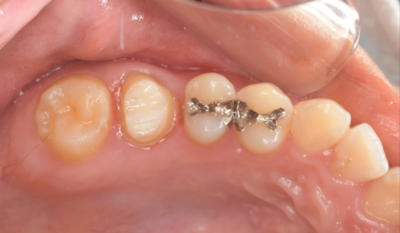

初診時口腔内写真

初診時パノラマX線写真と口腔内写真。

右上6に腫脹と排膿がみられた。